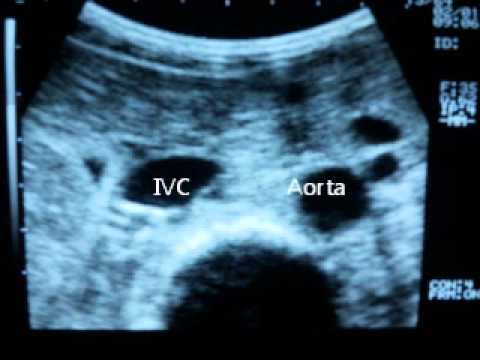

7. Assessment of Fluid Resuscitation by IVC Ultrasound :

how to assess volume status

11. Hot Tips - IVC Volume Assessment with Ultrasound :

14. Ultrasound assessment of volume status by caval index :